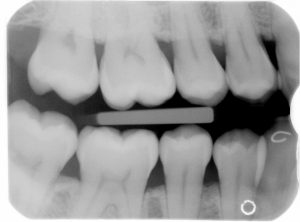

Wij kunnen niet alles in de mond zien. Met een röntgenfoto kunnen wij het kaakbot, situatie tussen de kiezen, situatie van de wortelpunt, etc. veel beter beoordelen, zodat wij tot een goede diagnose en behandelplan kunnen komen.

Meestal maken wij een kleine foto, maar als het noodzakelijk is, dan maken wij een kaakoverzichtsfoto.